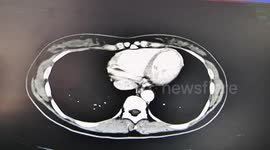

Shocking footage has emerged from China of a surgeon removing a spanner from an electrician's skull after he had a nasty accident at work.

The video, captured in Yuxi, Yunnan Province last Saturday, features the doctor explaining how the injury occured, as well as x-rays of the tool inside the man's head.

According to local reports, the electrician was working when the spanner fell off a 40-metre high platform, and stabbed him in the head.

The surgery took an hour-and-a-half with doctors saying the helmet saved his life.